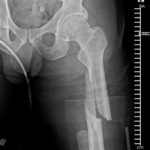

Vor ein paar Stunden wurde Steve deswegen im Palomar Medical Center Escondido operiert. Wie er selber berichtet, ist bei der OP an seinem Spiralbruch, linker Oberschenkel, alles perfekt abgelaufen.

An den Fotos unten kann man gut erkennen, dass der Knochen nun durch ein Titanstück und zwei Schrauben zusammengehalten wird. Den Moment des Sturzes hat Caballero auf Instagram hochgeladen. Den Clip findet ihr unter den Fotos.